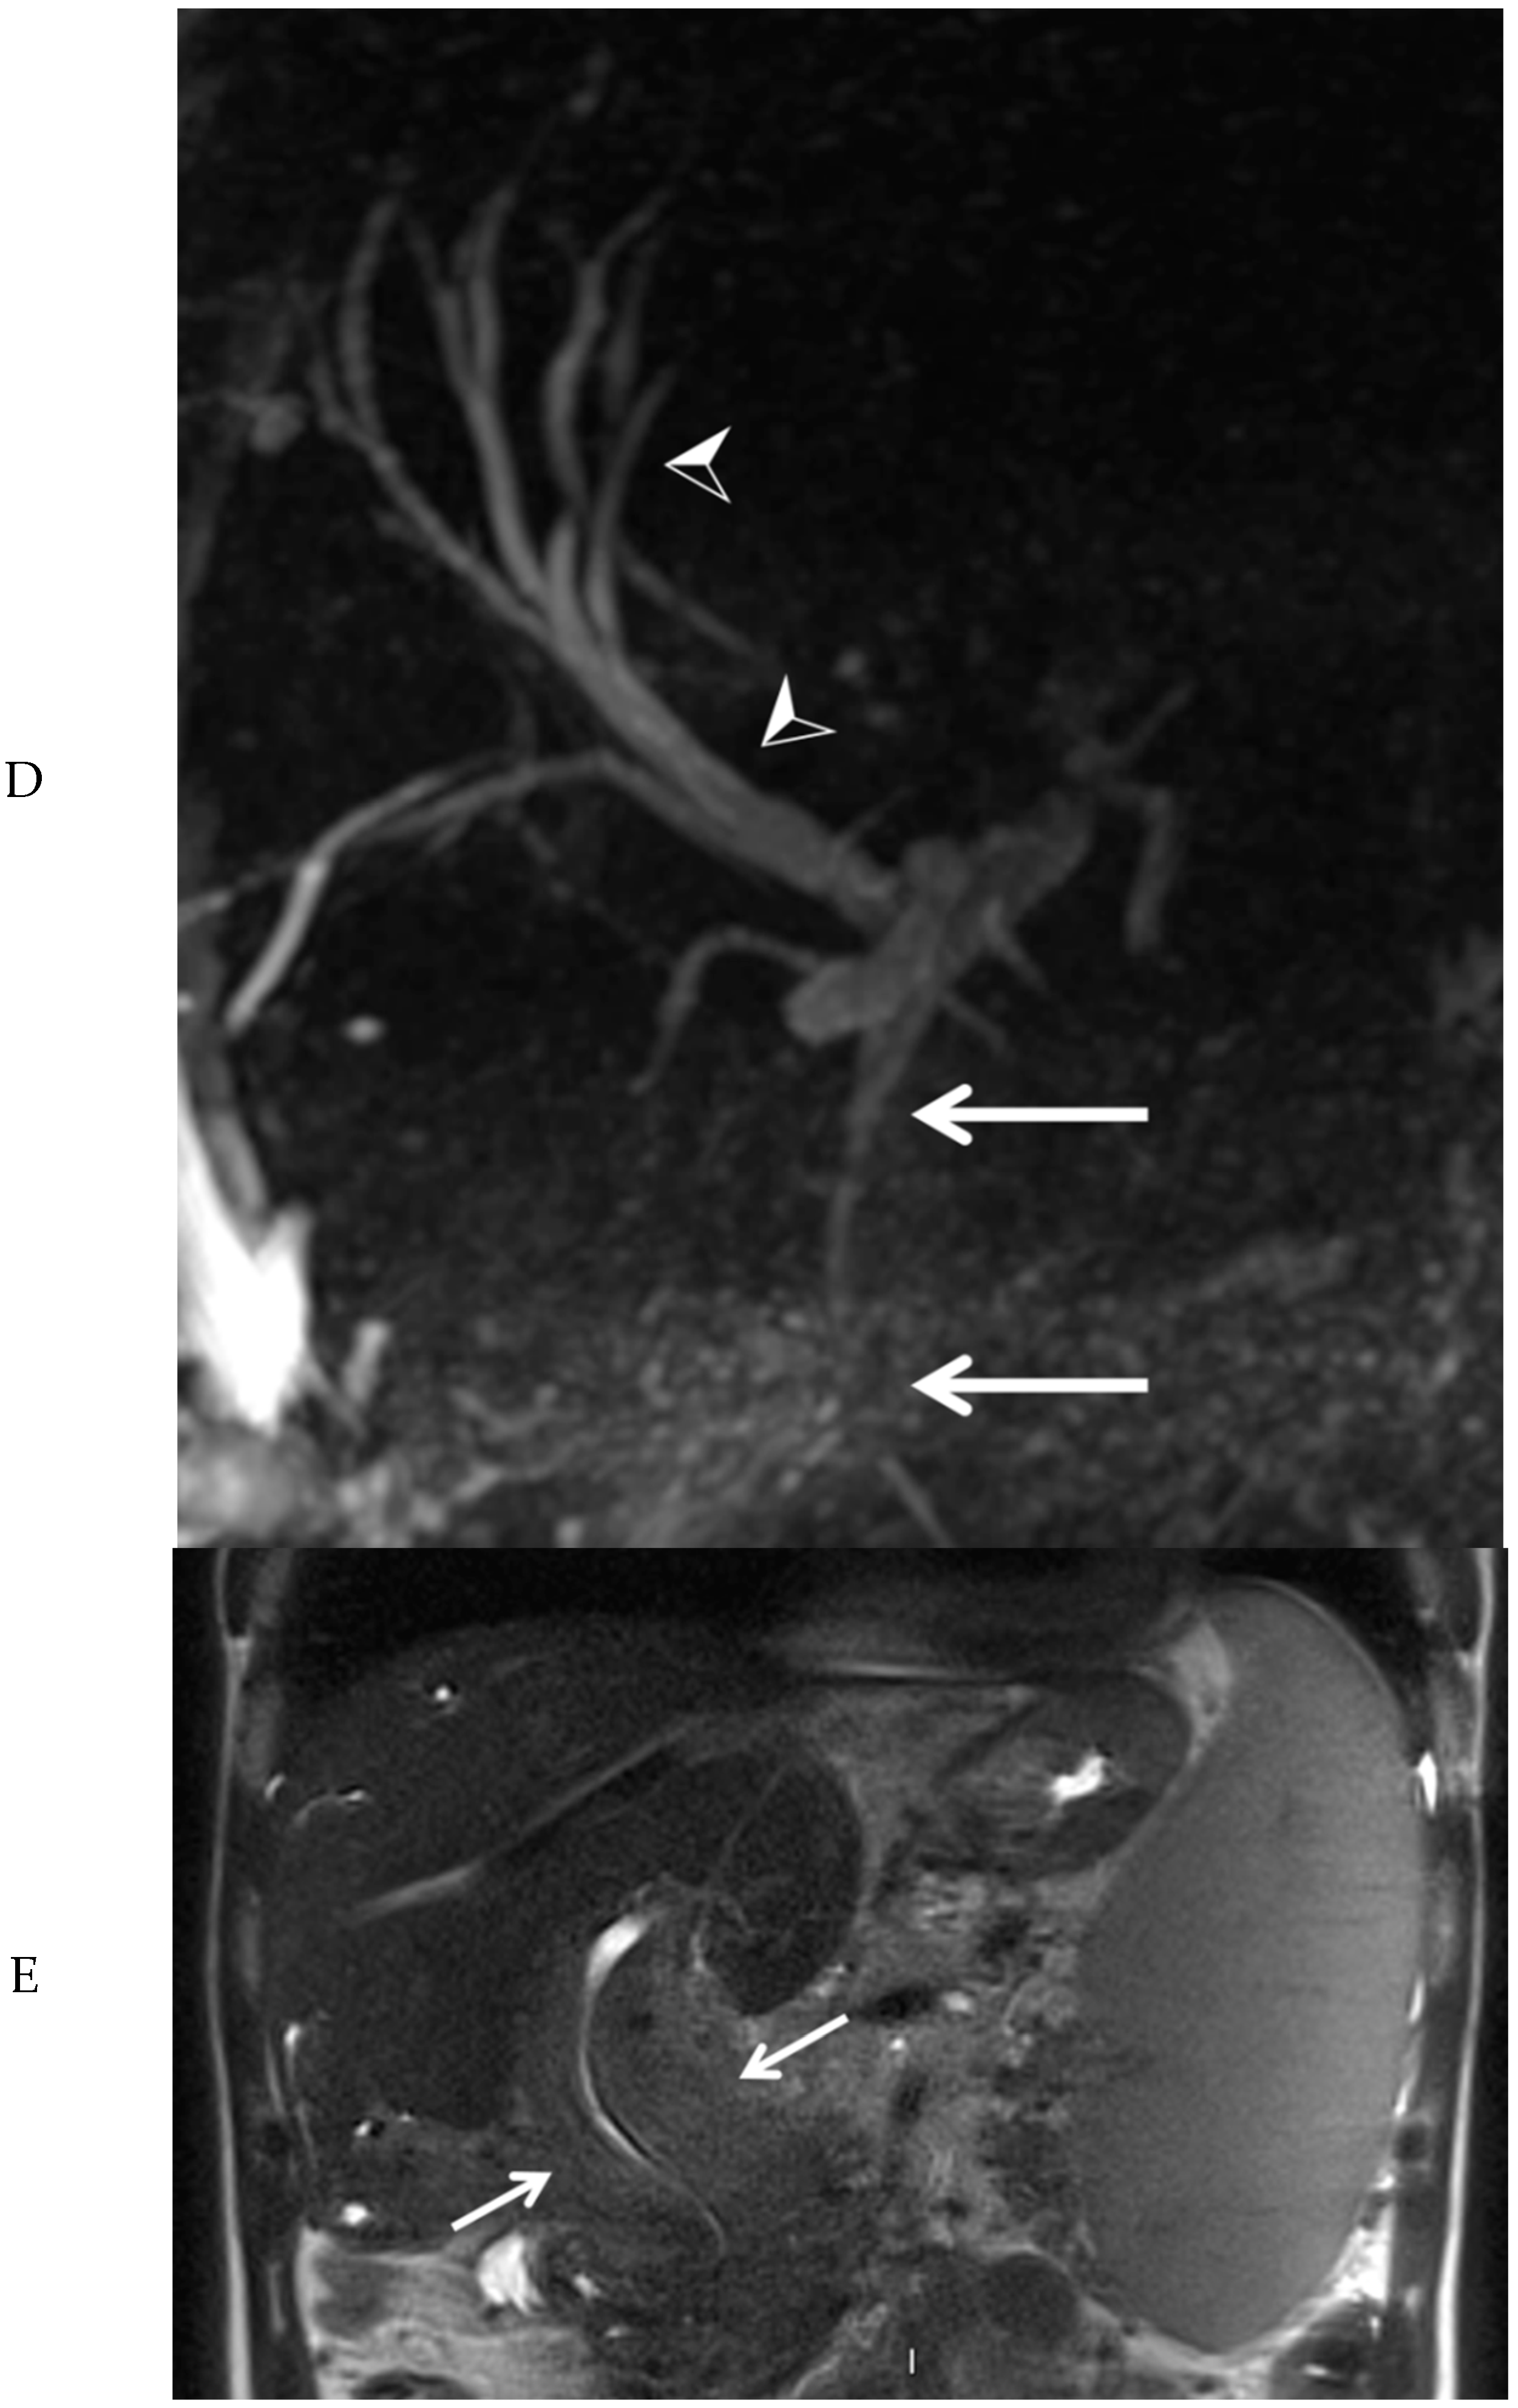

Subsequently, EUS combined with fine needle biopsy, and MRI of the upper abdomen were performed. EUS showed a highly vascular mass with a benign aspect. EUS-guided fine needle biopsy was somewhat difficult due to hardness of the mass. The histopathologic findings were most consistent with a lesion of vascular origin, such as hemangioma. MRI of the upper abdomen revealed a large mass surrounding the common bile duct, central intrahepatic bile ducts, cystic duct, and gallbladder, without diffusion restriction. After administration of intravenous contrast medium, no enhancement of the mass was visible in the arterial phase (Figure 3A). However, many small vessels were visible within the mass in the portal venous phase (Figure 3B), with diffuse homogeneous enhancement of the mass in the delayed phase (Figure 3C). At the MRCP, narrowing of the common bile duct was visible along its complete course, combined with dilation of the intrahepatic bile ducts (Figure 3D). At T2-weighted imaging, the mass around the narrowed common bile duct was slightly hyperintense when compared to the liver parenchyma (Figure 3E).

Figure 3. Magnetic resonance imaging of the mass in the upper abdomen (arrows). Shown are T1 weighted subtraction images of the mass in the upper abdomen with fat suppression after administration of intravenous contrast medium in the arterial (A), portal venous (B), and delayed phase (C). At magnetic resonance cholangiopancreaticography, narrowing of the common bile duct is visible along its complete course (arrows), combined with dilation of the intrahepatic bile ducts (arrowheads) (D). At T2-weighted imaging (E, coronal view), the mass surrounding the narrowed common bile duct was slightly hyperintense, when compared to the liver parenchyma (arrows).